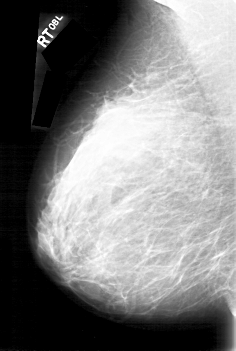

D_4092_1.LEFT_MLO

LEFT_MLO LINES 5386 PIXELS_PER_LINE 3721 BITS_PER_PIXEL 12 RESOLUTION 43.5 OVERLAY